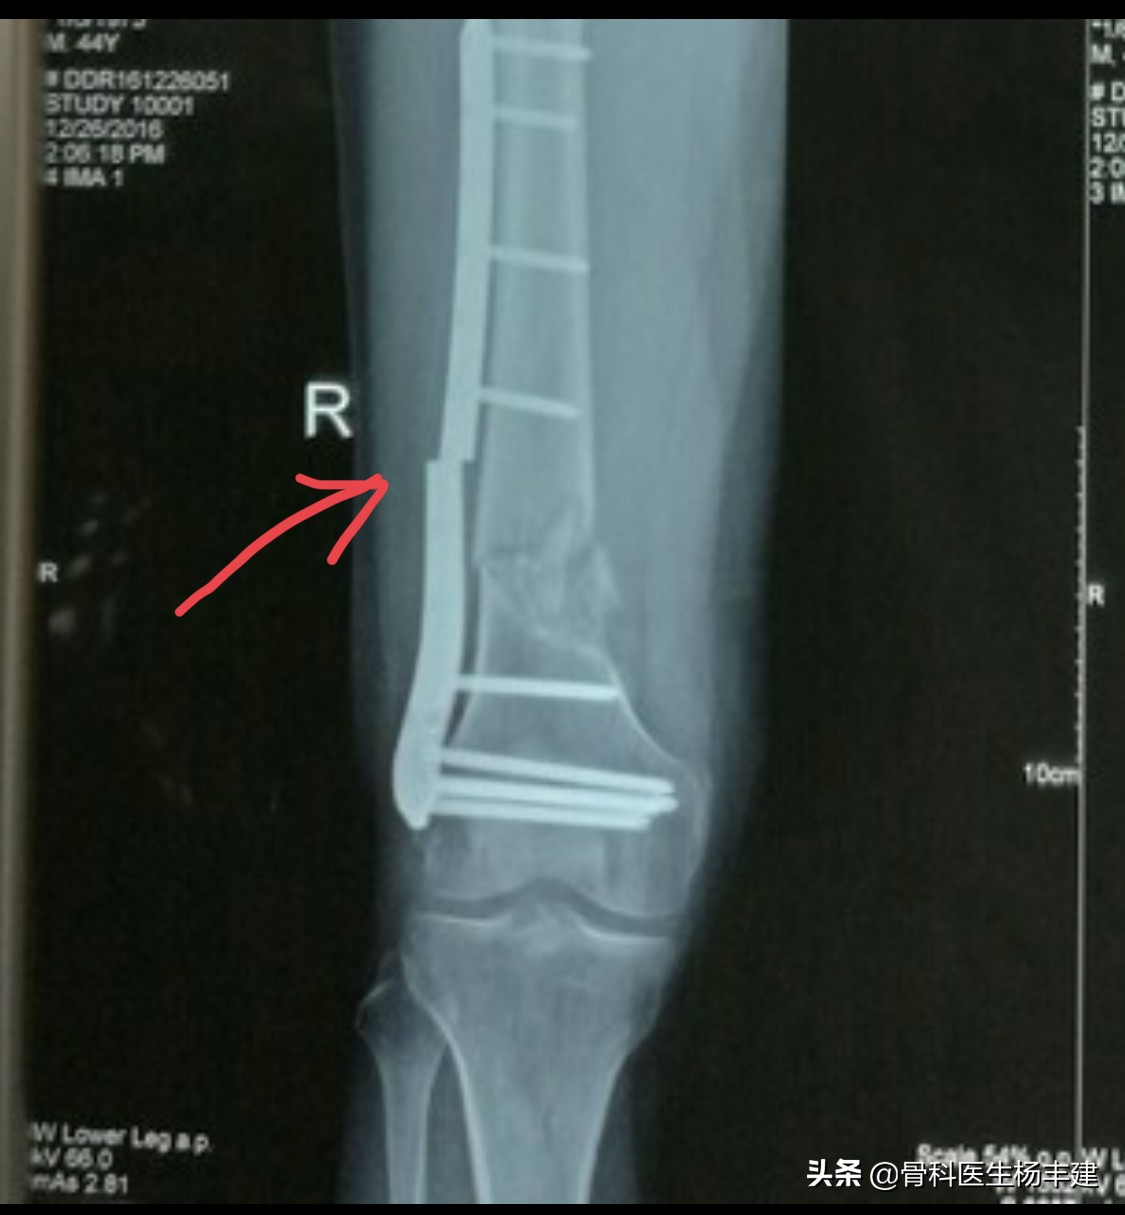

大腿骨固定后9个月,出现钢板断裂的病例

锁骨骨折后钢板断裂怎么办,股骨骨折钢板断裂原因分析

术后3个月不到出现断裂,钢板比较纤细是一方面原因